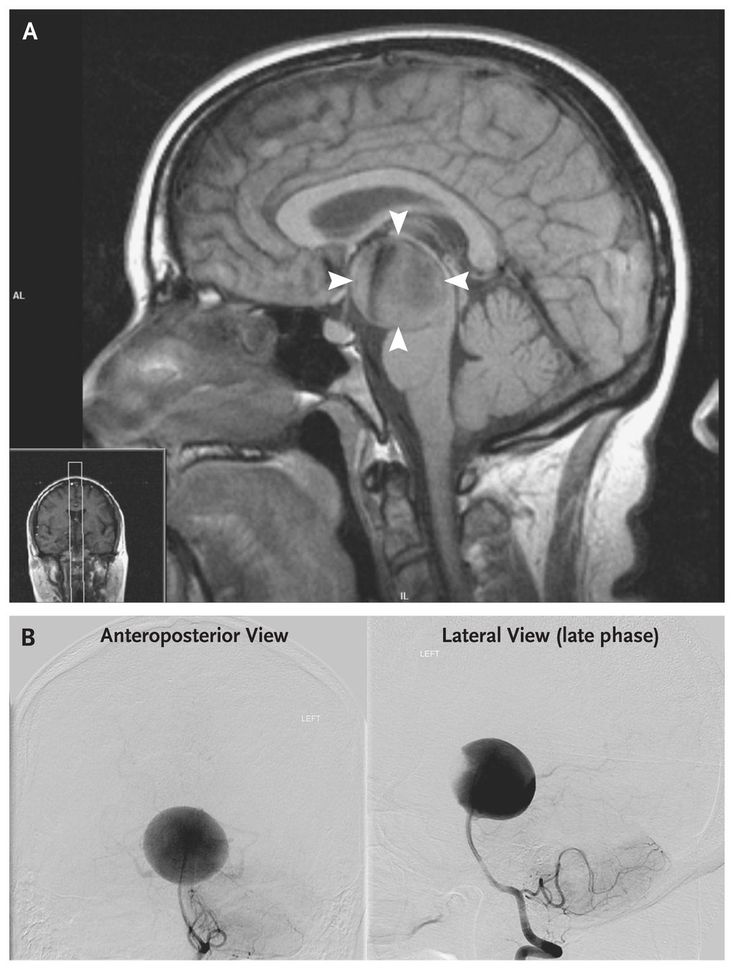

A 46-year-old right-handed woman presented with a 3-month history of occipital headache, progressive confusion, and personality change. Neurologic examination revealed mildly impaired smooth-pursuit eye movements, mildly impaired walking with a tandem gait, and a score of 30 out of 38 on the Kokmen Short Test of Mental Status (with a score of less than or equal to 29 indicating dementia). Computed tomography of the head revealed a circumferential midbrain lesion with mass effect and hydrocephalus. Magnetic resonance imaging (MRI) and magnetic resonance angiography revealed an aneurysm (3.5 cm by 4 cm) (Panel A, arrowheads; the inset indicates the imaging plane) at the bifurcation of the basilar artery, with compression of the midbrain and probably the mamillary body; these findings were confirmed by cerebral angiography (Panel B). Because the aneurysm incorporated the origin of both posterior cerebral arteries, it was not amenable to safe direct surgical clipping or to endovascular embolization. A surgical clip was used to occlude the basilar artery below the origin of the superior cerebellar arteries to reverse the flow and promote aneurysm thrombosis; this permitted adequate collateralization to the top of the basilar territory through the posterior communicating artery. The patient was discharged home 3 days after the procedure, with no neurologic deficits. Follow-up MRI 1 month later revealed persistent filling of the aneurysm through collateral vessels. She died suddenly 6 weeks after treatment, possibly owing to progressive hydrocephalus or delayed aneurysm rupture. No autopsy was performed.